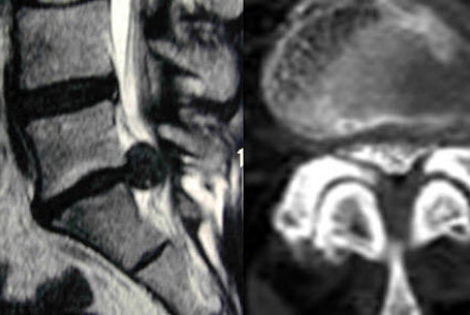

内視鏡下椎間板摘出術

PED / 内視鏡下椎間板ヘルニア摘出術

体への負担が少ない内視鏡下椎間板ヘルニア摘出術

(PED:Percutaneous Endoscopic Discectomy)

椎間板ヘルニアは、背骨の骨と骨の間でクッション材の役割を果たす椎間板の一部が飛び出して神経を圧迫し、手足に痛みやしびれが生じる病気です。

当院は、中度~重度の椎間板ヘルニアの治療方法として、体への負担が少ない内視鏡下椎間板ヘルニア摘出術(PED:Percutaneous Endoscopic Discectomy)を取り入れています。

PEDでは、直径6~7mmの鉗子をヘルニアの部位に挿入し、内視鏡画像をモニターに拡大表示しながら行います。

PEDの場合、局部麻酔による手術となり、短時間(1~2時間ほど)で終わります。また、傷口は6~7mm程度で、抜糸も必要ありません。早くて手術翌日には退院できるため、体に優しい手術と言えるでしょう。